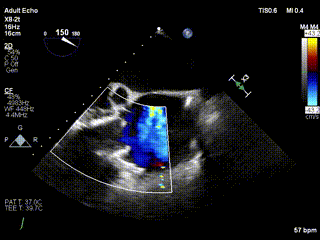

2021年12月24日,復(fù)旦大學(xué)附屬中山醫(yī)院葛均波院士團隊成功應(yīng)用LuX-Valve Plus為一例極重度三尖瓣反流(TR)合并房顫、房缺的患者完成了經(jīng)血管三尖瓣置換術(shù),這是在前基礎(chǔ)上,本周完成的第三例經(jīng)血管三尖瓣置換手術(shù),葛均波院士、周達(dá)新教授等與心外科魏來教授、賴顥教授,心超室的潘翠珍教授、李偉教授及麻醉科的郭克芳教授共同完成了本周手術(shù),均獲得圓滿成功!患者術(shù)后超聲顯示無TR,臨床癥狀明顯改善。本周手術(shù)的成功也為LuX-Valve Plus救治性臨床研究添上了濃墨重彩的一筆。

三例患者入院后,葛均波院士團隊周達(dá)新教授、潘文志教授、張源博士、陳莎莎博士及心超室的潘翠珍教授、李偉教授對患者的情況進行詳細(xì)評估和討論,最終決定為三例患者選擇LuX-Valve Plus40mm、50mm和50mm型號的瓣膜進行手術(shù)治療。手術(shù)后即刻拔除氣管插管,術(shù)后患者三尖瓣反流癥狀得到顯著改善,復(fù)查心超結(jié)果顯示人工三尖瓣瓣膜支架固定穩(wěn)定,瓣葉關(guān)閉形態(tài)未見異常,未見明顯反流。